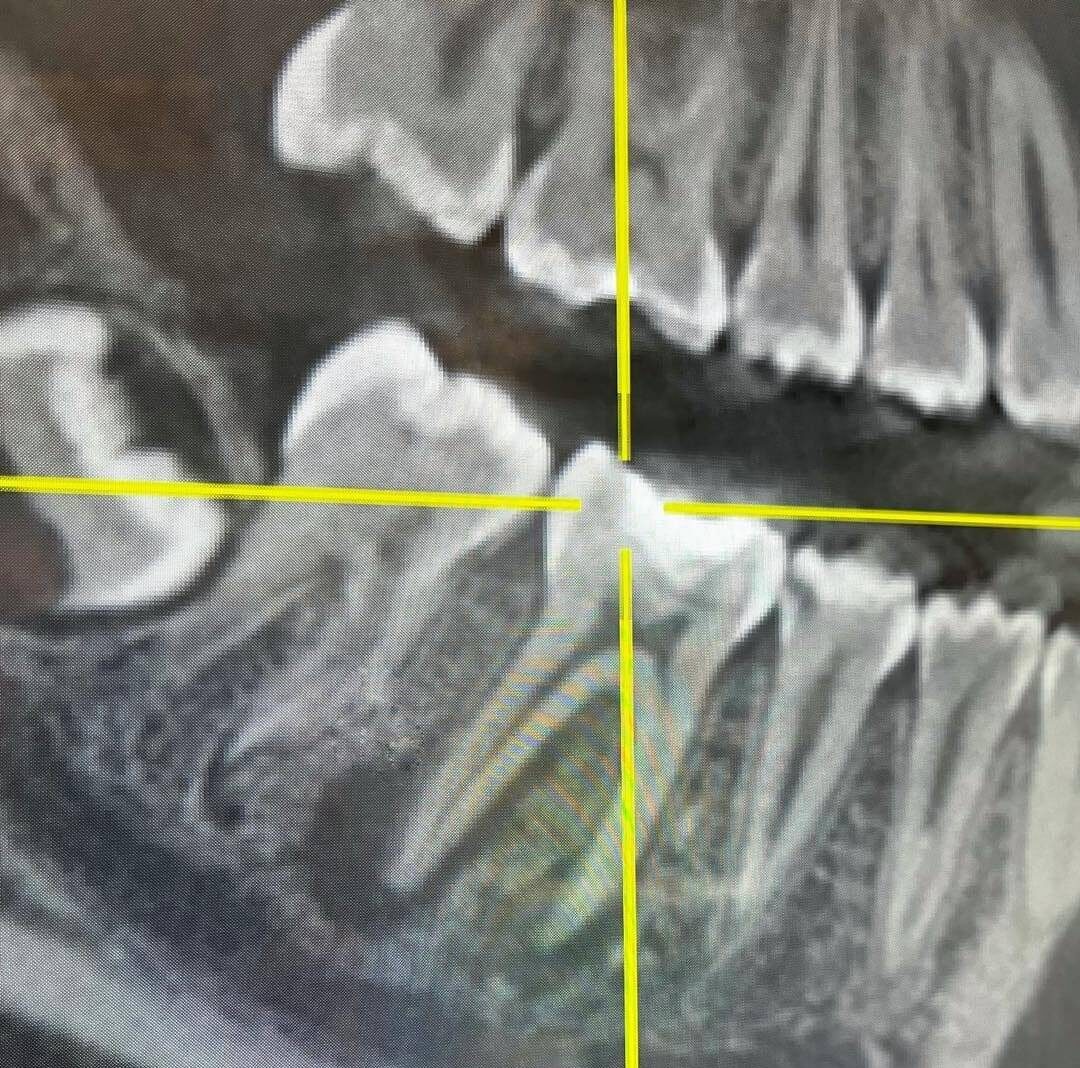

Synopsis Maintaining dental implants is necessary for their longevity and overall oral health. At Origin Dental Wellness in Tulsa, we recommend proper care to protect your investment and keep your smile healthy. We explore some vital maintenance steps, common mistakes to avoid, and factors influencing dental implant costs. By following a consistent routine and addressing … Read more